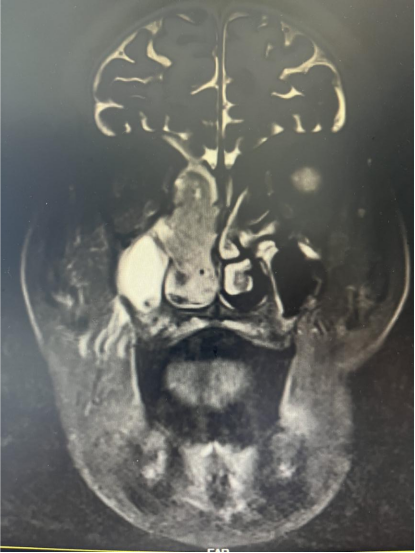

(鼻窦MRI)

住院后更全面、精准的检查后,发现老人鼻子里的肿块已经靠近眼睛和颅底,而肿块活检报告也和预估一致:鼻恶性肿瘤。随后,由章程副院长、赵礼君主任领衔的医疗团队进行了数次讨论,结合目前学科诊疗进展,一致认为手术+术后进一步治疗是最有效、最值得推荐的治疗方案。"对于高龄患者,我们不仅要考虑手术本身,更要全面评估其身体承受能力,确保治疗安全。"耳鼻喉科主任医师章程介绍。